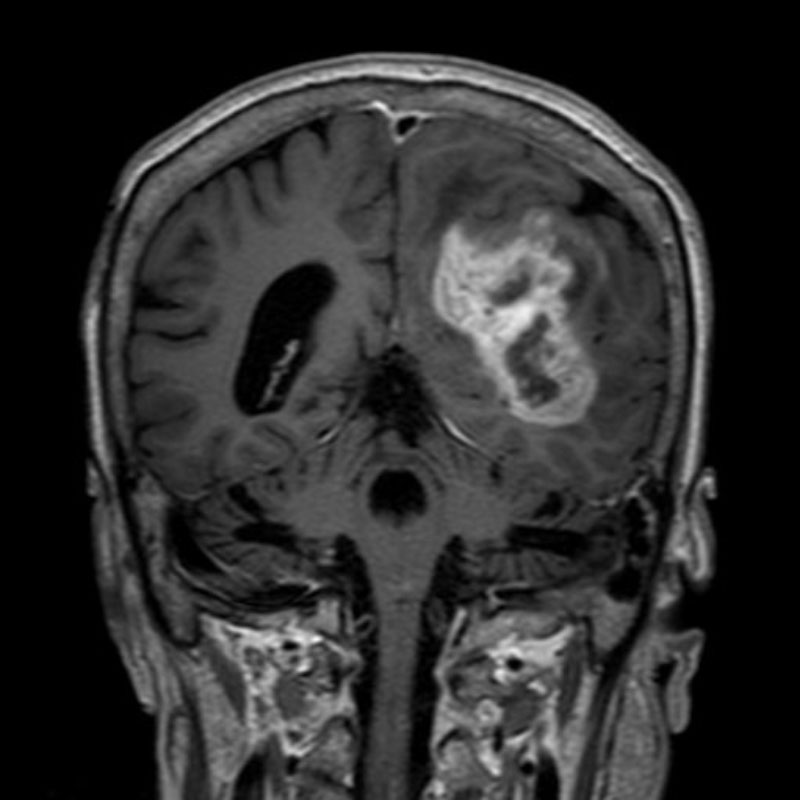

640

'25年6月

80代

傍矢状洞髄膜腫

頭蓋内腫瘍摘出術

No.’25_42 手術前1

No.’25_42 手術前2

No.’25_42 摘出 前

No.’25_42  摘出 中

No.’25_42 摘出 後